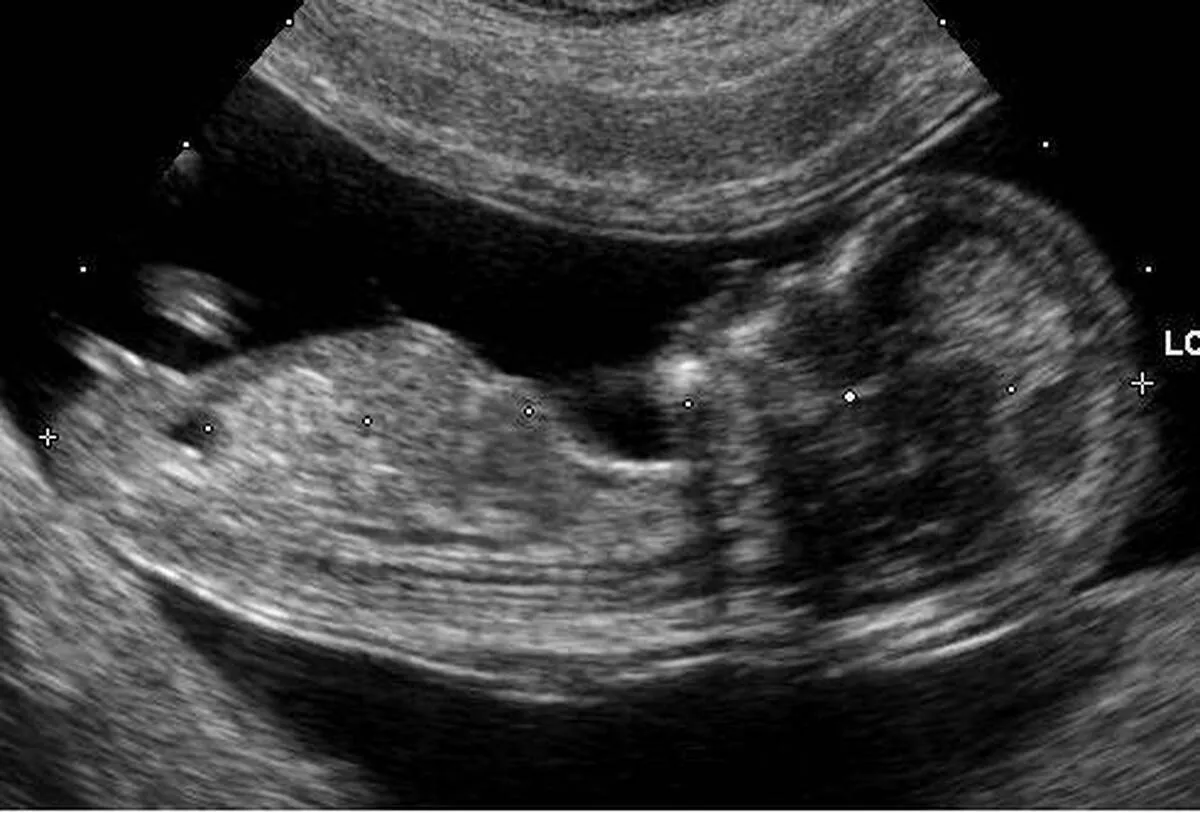

«سونوگرافی» در سینما حقیقت روشنگری کرد/ روایت مستند از زنده به گور کردن دختران با شیوه‌های مدرن

مستند «سونوگرافی» که در هفدهمین جشنواره سینما حقیقت به نمایش درآمد، از یک رفتار نامطلوب درباره تولد نوزادان پرده برداشت.

به گزارش گروه فرهنگ و جامعه خبرگزاری علم و فناوری آنا، گرایش به داشتن فرزند پسر موجب شده تا سقط جنین دختر با افزایش همراه شود.

مستند «سونوگرافی» به کارگردانی‌ هایده مرادی از باوری غلط پرده برداشته که در بین برخی خانواده‌ها رواج یافته است. این مستند در هفدهمین دوره از جشنواره سینما حقیقت اکران شد.

این باور هنوز وجود دارد و  اصرار به داشتن فرزند پسر، جهلی است که ریشه‌ها و علت‌های آن در مستند «سونوگرافی» بررسی شده است. در این مستند، پزشکان زنان اذعان دارند که مادران باردار تمایل دارند فرزند پسر داشته باشند و به‌ندرت علاقه‌مند به داشتن فرزند دختر هستند. یکی از پزشکان می‌گوید، برخی حتی بعد از سونوگرافی و پی بردن به جنسیت فرزند خود، دختر را سقط می‌کنند و برخی از ما رژیم غذایی و دارویی می‌خواهند که فرزندشان پسر شود.